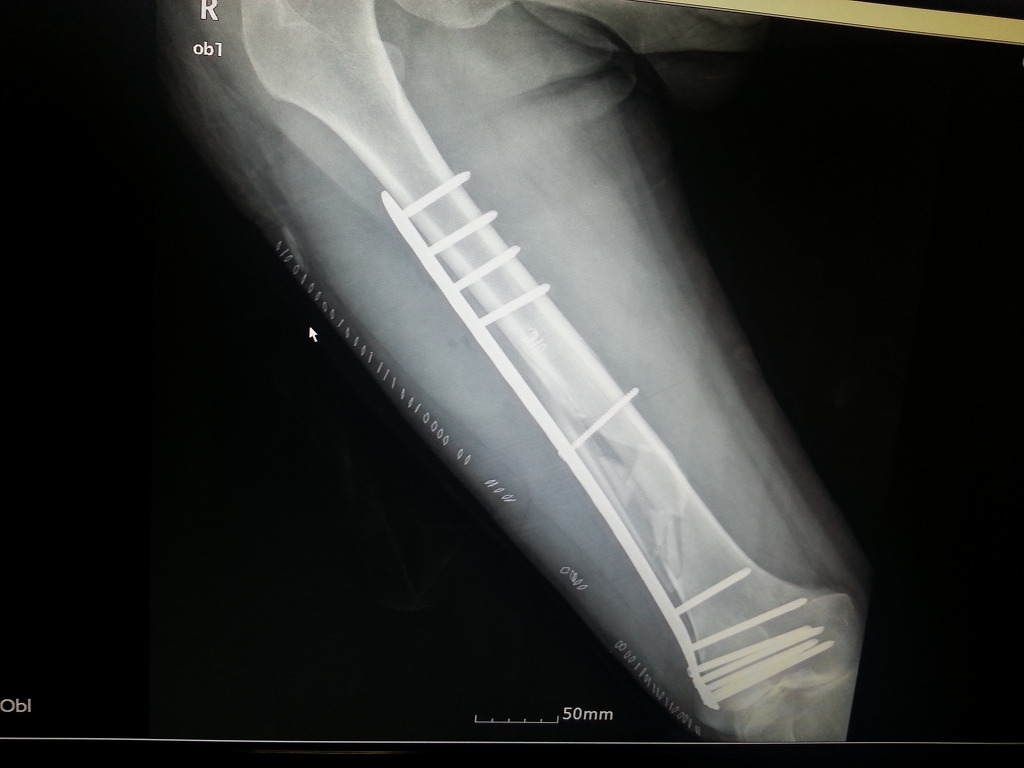

2013년 4월에 대퇴골 골절로 금속판 고정술을 받았습니다

어제 엑스레이결과 철심제거 스케줄 잡자고 하시네요